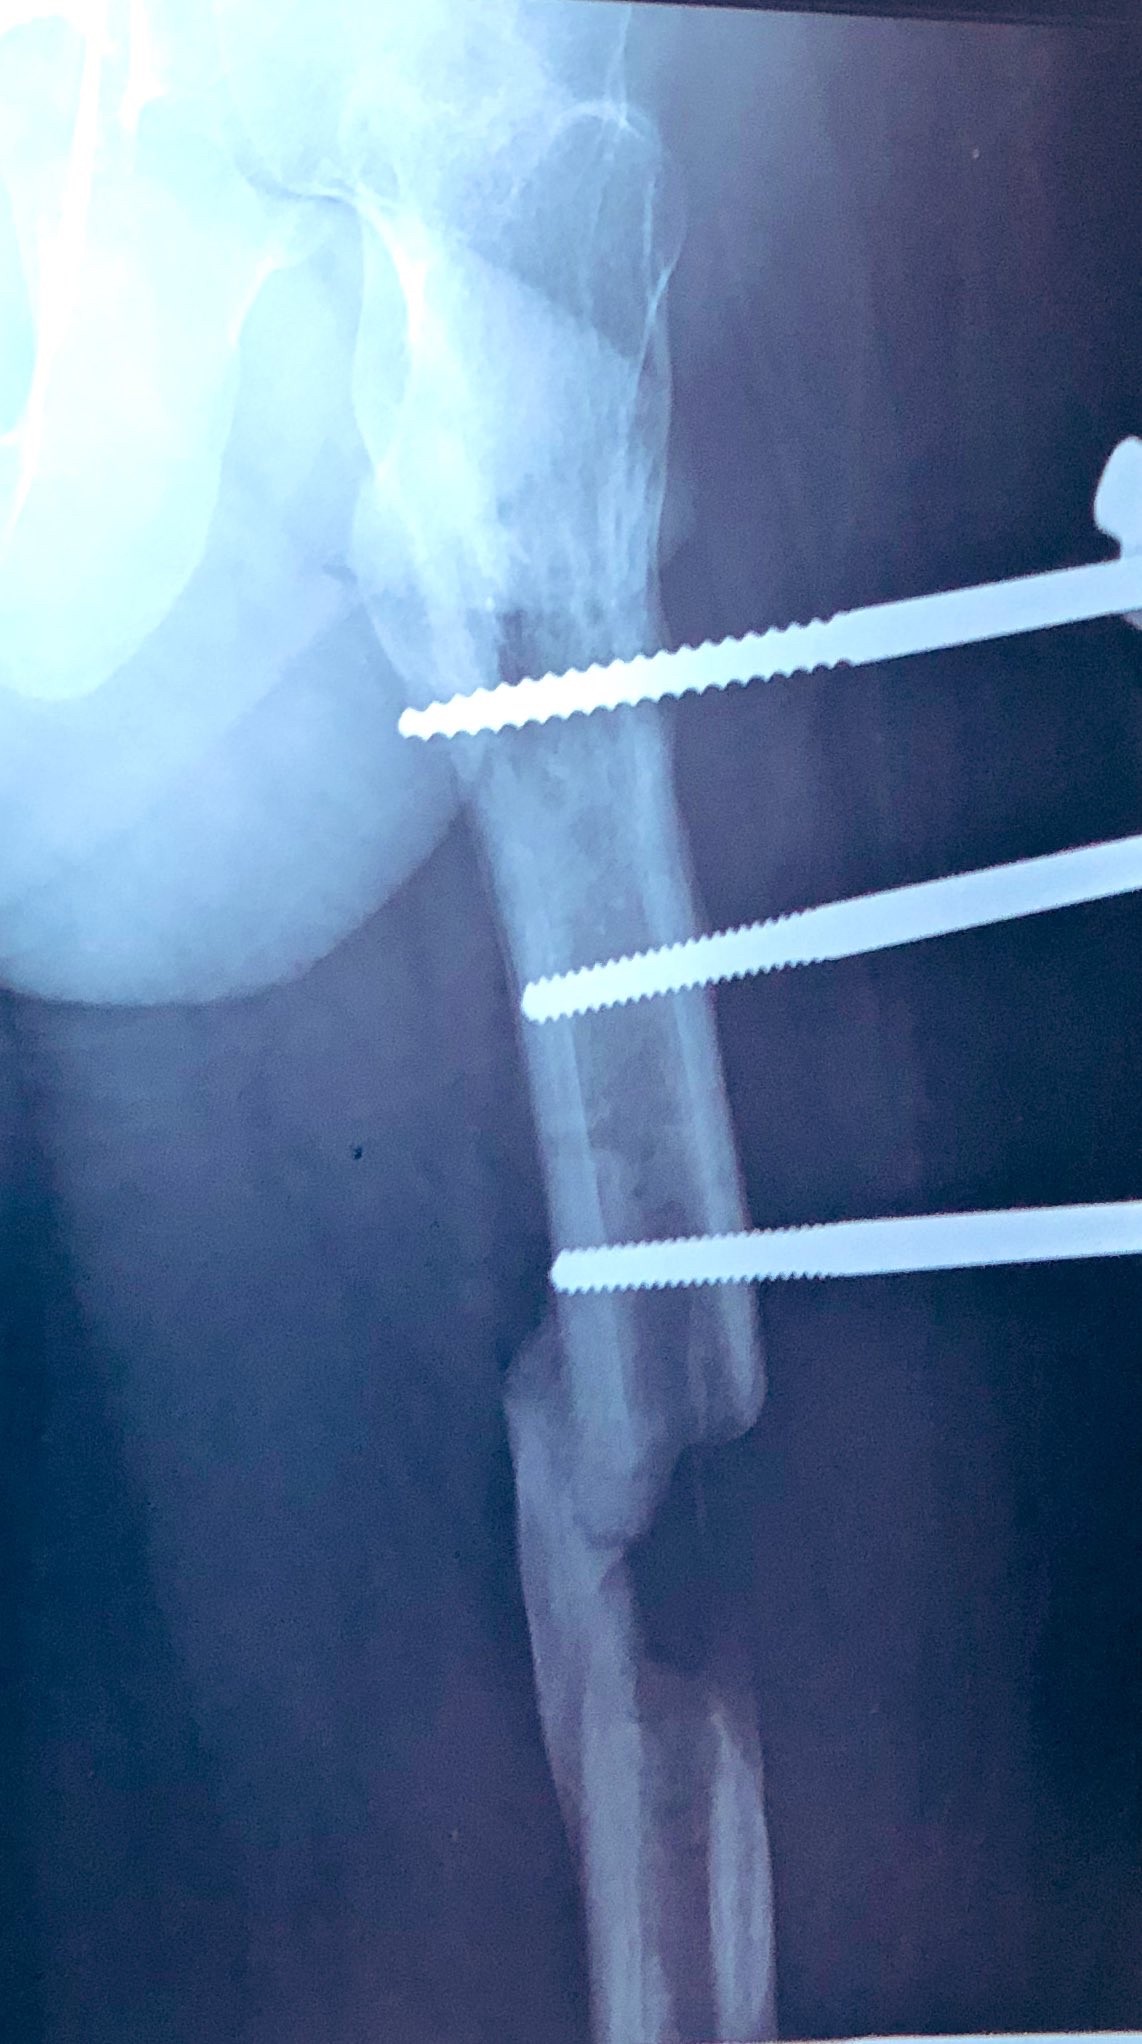

もうおしまいだよこの骨

ヤバいでしょ

骨欠けてますよ

骨、グニャンw

骨伸ばすのは分かるんやが皮膚や筋肉はどうなんの?

一緒に伸びてくる

手足切断しても皮膚や筋肉は上手いこと現状に合わせに来るもんなんや

問題は新しい骨の強度とバランス